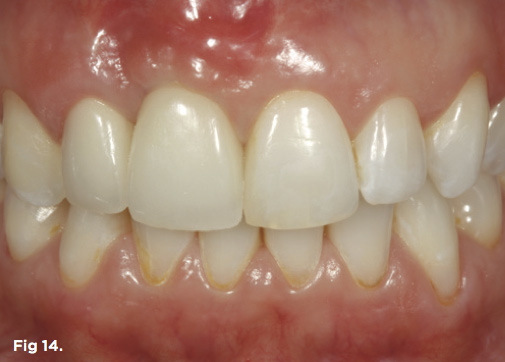

A 38-year-old Caucasian female patient presented with a high smile line and loss of the papilla between tooth No. 7 and edentulous adjacent site No. 8 (Figure 1). Understandably, the patient was unhappy and embarrassed about her esthetic condition. Her dental history revealed tooth replacement of No. 8 with an implant that eventually failed. The site had been previously bone grafted upon implant removal. She was given a composite pontic No. 8 bonded to a tooth No. 7 composite veneer as a transitional restoration. The implant was positioned too close to the proximal surface of tooth No. 7, which stripped the periodontal attachment of the root and ultimately caused loss of the papilla (Figure 2). As previously outlined, the treatment sequence would be to first provide a provisional restorative solution to evaluate the projected outcomes and assess if the patient was willing to undergo orthodontic therapy. In this situation, a full-coverage crown No. 7 with a cantilevered pontic No. 8, with artificial acrylic gingiva to replace the lost papilla on the mesial aspect of tooth No. 7 was used as a transitional temporary prosthesis (Figure 3). In addition, a composite resin restoration was placed on the mesial aspect of tooth No. 9 to restore its individual tooth proportion and shape. The patient’s esthetic outcome could now be evaluated with restorative correction alone; it was therefore mutually determined that the correction of her deformity would best be served with additional orthodontic forced eruption therapy. A fixed orthodontic appliance (brackets) was bonded to the teeth and temporary prosthesis. The level of the interproximal pink acrylic was used as a therapeutic guide for the amount of forced eruption required as well as the alignment of the mesial papilla of No. 7 to that of the adjacent papillae height (Figure 4). Floss was used to elevate the amount of vertical movement achieved relative to the adjacent papilla tooth No. 9. Eventually, all the artificial pink acrylic was removed. (Note that the distal papilla on tooth No. 7 also comes more incisal—in fact, it is slightly excessive at the endpoint of treatment [Figure 5]). However, the distal papilla and midfacial tissues of tooth No. 7 can be reshaped through clinical crown lengthening toward the end of treatment prior to definitive restoration, thereby restoring the proper papilla height-to-tooth ratio of 40%. After stabilization of tooth No. 7 for a minimum of 6 months post-orthodontics, an implant was placed in site No. 8. A papilla-sparing incision design was used for flap elevation (Figure 6), bone allograft was used to further augment the facial aspect of the ridge simultaneously with implant placement (Figure 7), and a resorbable membrane was used for guided bone regeneration.

Fig 1. Preoperative extraoral view of patient with significant loss of the papilla on the mesial aspect of tooth No. 7 and a high smile line.

Figure 1

Fig 14. The definitive restoration, a tooth No. 7 crown splinted to implant crown No. 8, shows harmony in regard to the natural dentition as well as the reconstructed gingival architecture, which was improved employing forced orthodontic tooth eruption.

Figure 14

After 6 months of healing of the implant, stage 2 uncovering was performed and the mucosal tissues were allowed to mature for another 2 to 3 weeks. A temporary screw-retained implant cylinder was joined to the implant and acrylic crown (Figure 8). The subgingival shape of the temporary was modified with additional acrylic and the technique of non-surgical tissue sculpting, which was developed to provide the proper emergence profile to the mucosal tissues.27 It is important that the temporary blanching (ischemia) of the mucosal tissues dissipate after 10 minutes (Figure 9). After 3 weeks, soft-tissue scalloping through gingivectomy was done to recreate the proper shape (ie, gingival zenith)28 and proportion for the mucosal tissues (Figure 10). Fiberotomy on the distal aspect of tooth No. 7 was not performed during treatment; therefore, this papilla was slightly more incisal (longer) than the adjacent papillae (Figure 11). A final impression was made of crown No. 7 and implant No. 8 at the implant level to enable a working cast to be made in the laboratory. An all-ceramic custom abutment was made for implant No. 8, and splinted full-coverage units were made for crowns No. 7 and No. 829 (Figure 12). The custom abutment was seated intraorally and torqued according to the manufacturer’s recommendation. The crowns were luted with provisional cement and maintained at 4-month recall intervals (Figure 13). Note the health of the periodontal tissues and its integration with the adjacent teeth and surrounding gingiva, taking a complex esthetic and functional problem for a patient with a high smile line and providing a predictable restorative and esthetic outcome (Figure 14).